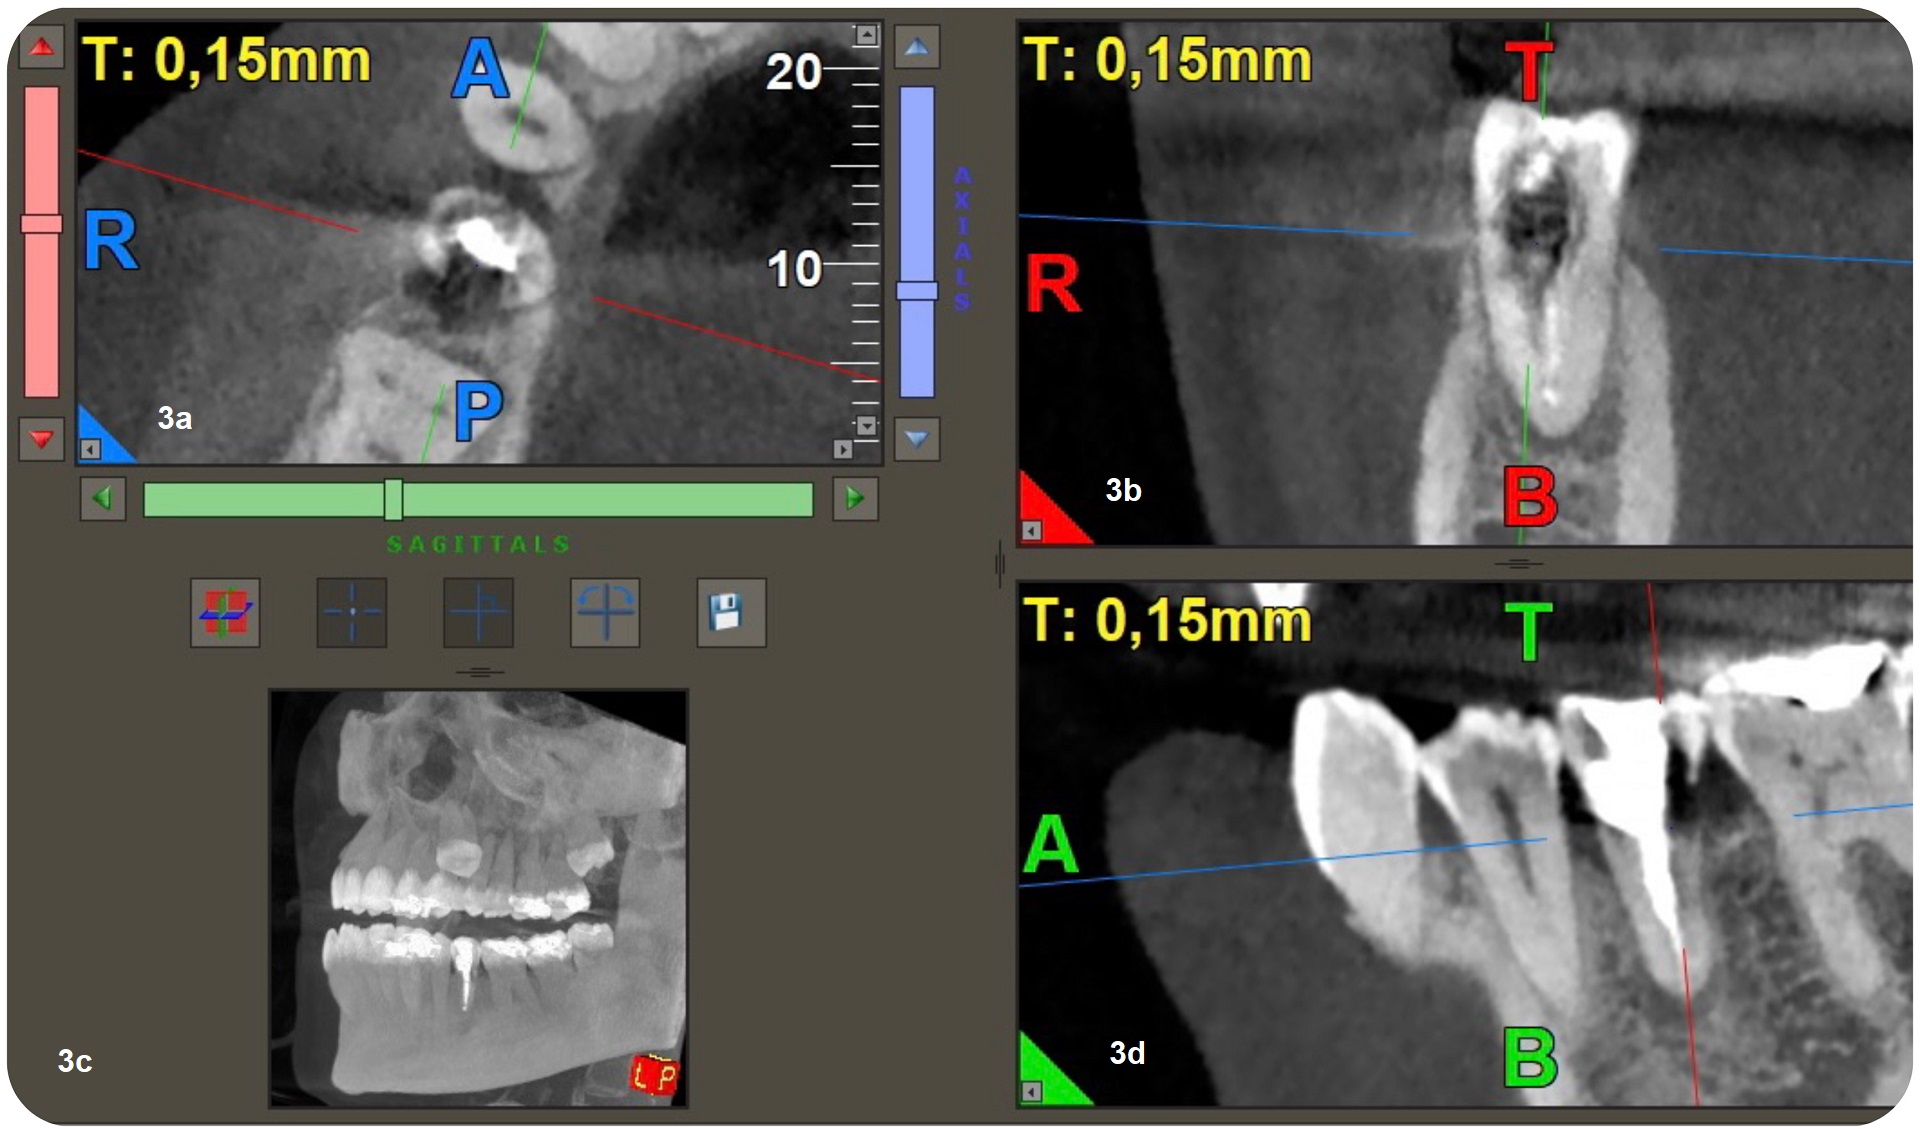

The radiographic examination showed periapical radiolucency and a radiolucent lesion in the cervical area of the tooth (Figs. 1 & 2). To determine the extent and depth of the lesion, a CBCT scan was performed (Fig. 3). Based on the CBCT images and 3D reconstructions, a diagnosis of Heithersay Class III external cervical invasive root resorption (ECIR) was determined in an endodontically treated tooth with symptomatic periapical periodontitis. The patient was informed of the diagnosis, treatment plan alternatives and prognosis of the case.

Figs. 3a–d: 3D reconstruction of axial section showing extension in mesial-distal direction (a). 3D reconstruction of a sagittal section showing the lesion extension, buccal-palatal direction (b). Coronal section of CBCT showing the extension of the periapical lesion and the resorptive defect (c). CBCT scan (d).

CBCT is a useful tool in endodontics, being used to assess the extent of an external cervical resorption defect, to detect and classify periapical periodontitis and to assess anatomical references with greater accuracy. Various studies have proved that CBCT is very helpful in diagnosis of this type of resorption.2–4 In the clinical case presented, an apical lesion and ECIR were observed, and CBCT was used to observe the size of the periapical lesion and the size and location of the resorption defect at the three spatial levels.